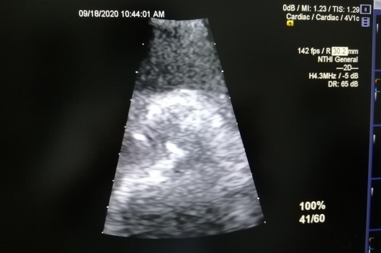

心脏杂音是由于心腔或大血管内的血液流动紊乱形成旋涡,使心室壁、心瓣膜或血管壁发生震动而产生,也可以是由于血流经过心腔或心瓣膜时速度增快而产生。心脏杂音一般可分为两类:一类是生理性或功能性杂音,轻而柔和,多发生于正常青年人,也见于发热、贫血、情绪激动、运动后及有甲状腺功能亢进症的患者;另一类是病理性或器质性杂音,可见于先天性心脏病、冠心病、风湿性心脏病、心肌病等各类心脏病。对有病理性杂音者要格外引起重视,需要行心脏彩超等检查进一步明确诊断。该患者经心脏彩超检查确诊为主动脉瓣二瓣畸形、主动脉瓣重度狭窄合并轻度关闭不全。

主动脉瓣二瓣畸形